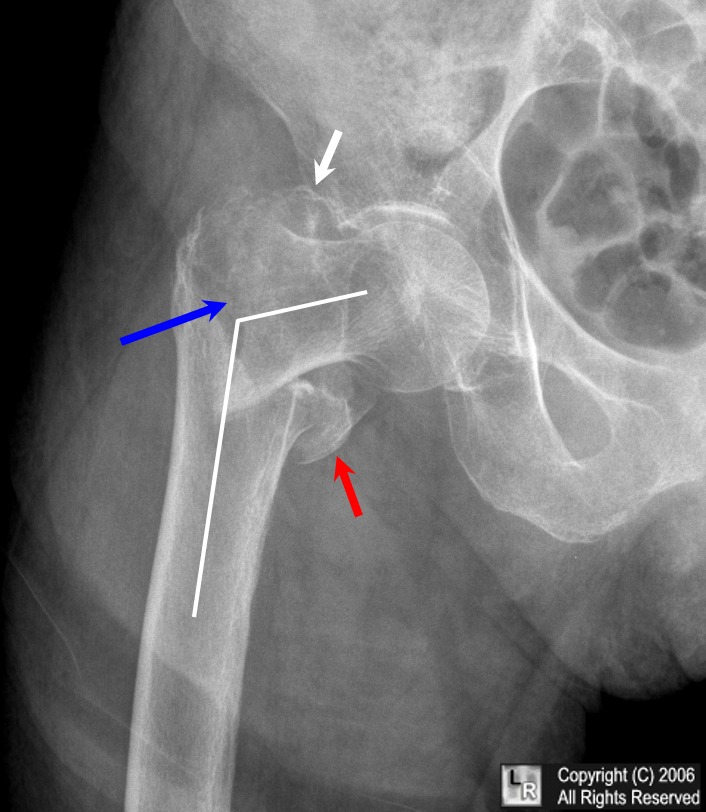

Lo studio ha esaminato 171 pazienti con una frattura pertrocanterica che si verifica tra il collo del femore e una prominenza ossea inferiore chiamata piccolo trocantere. I pazienti sono stati assegnati in modo casuale a uno dei due gruppi: un gruppo ha ricevuto Teriparatide dopo l’intervento chirurgico e un gruppo ha ricevuto un altro farmaco comunemente usato per curare l’osteoporosi.